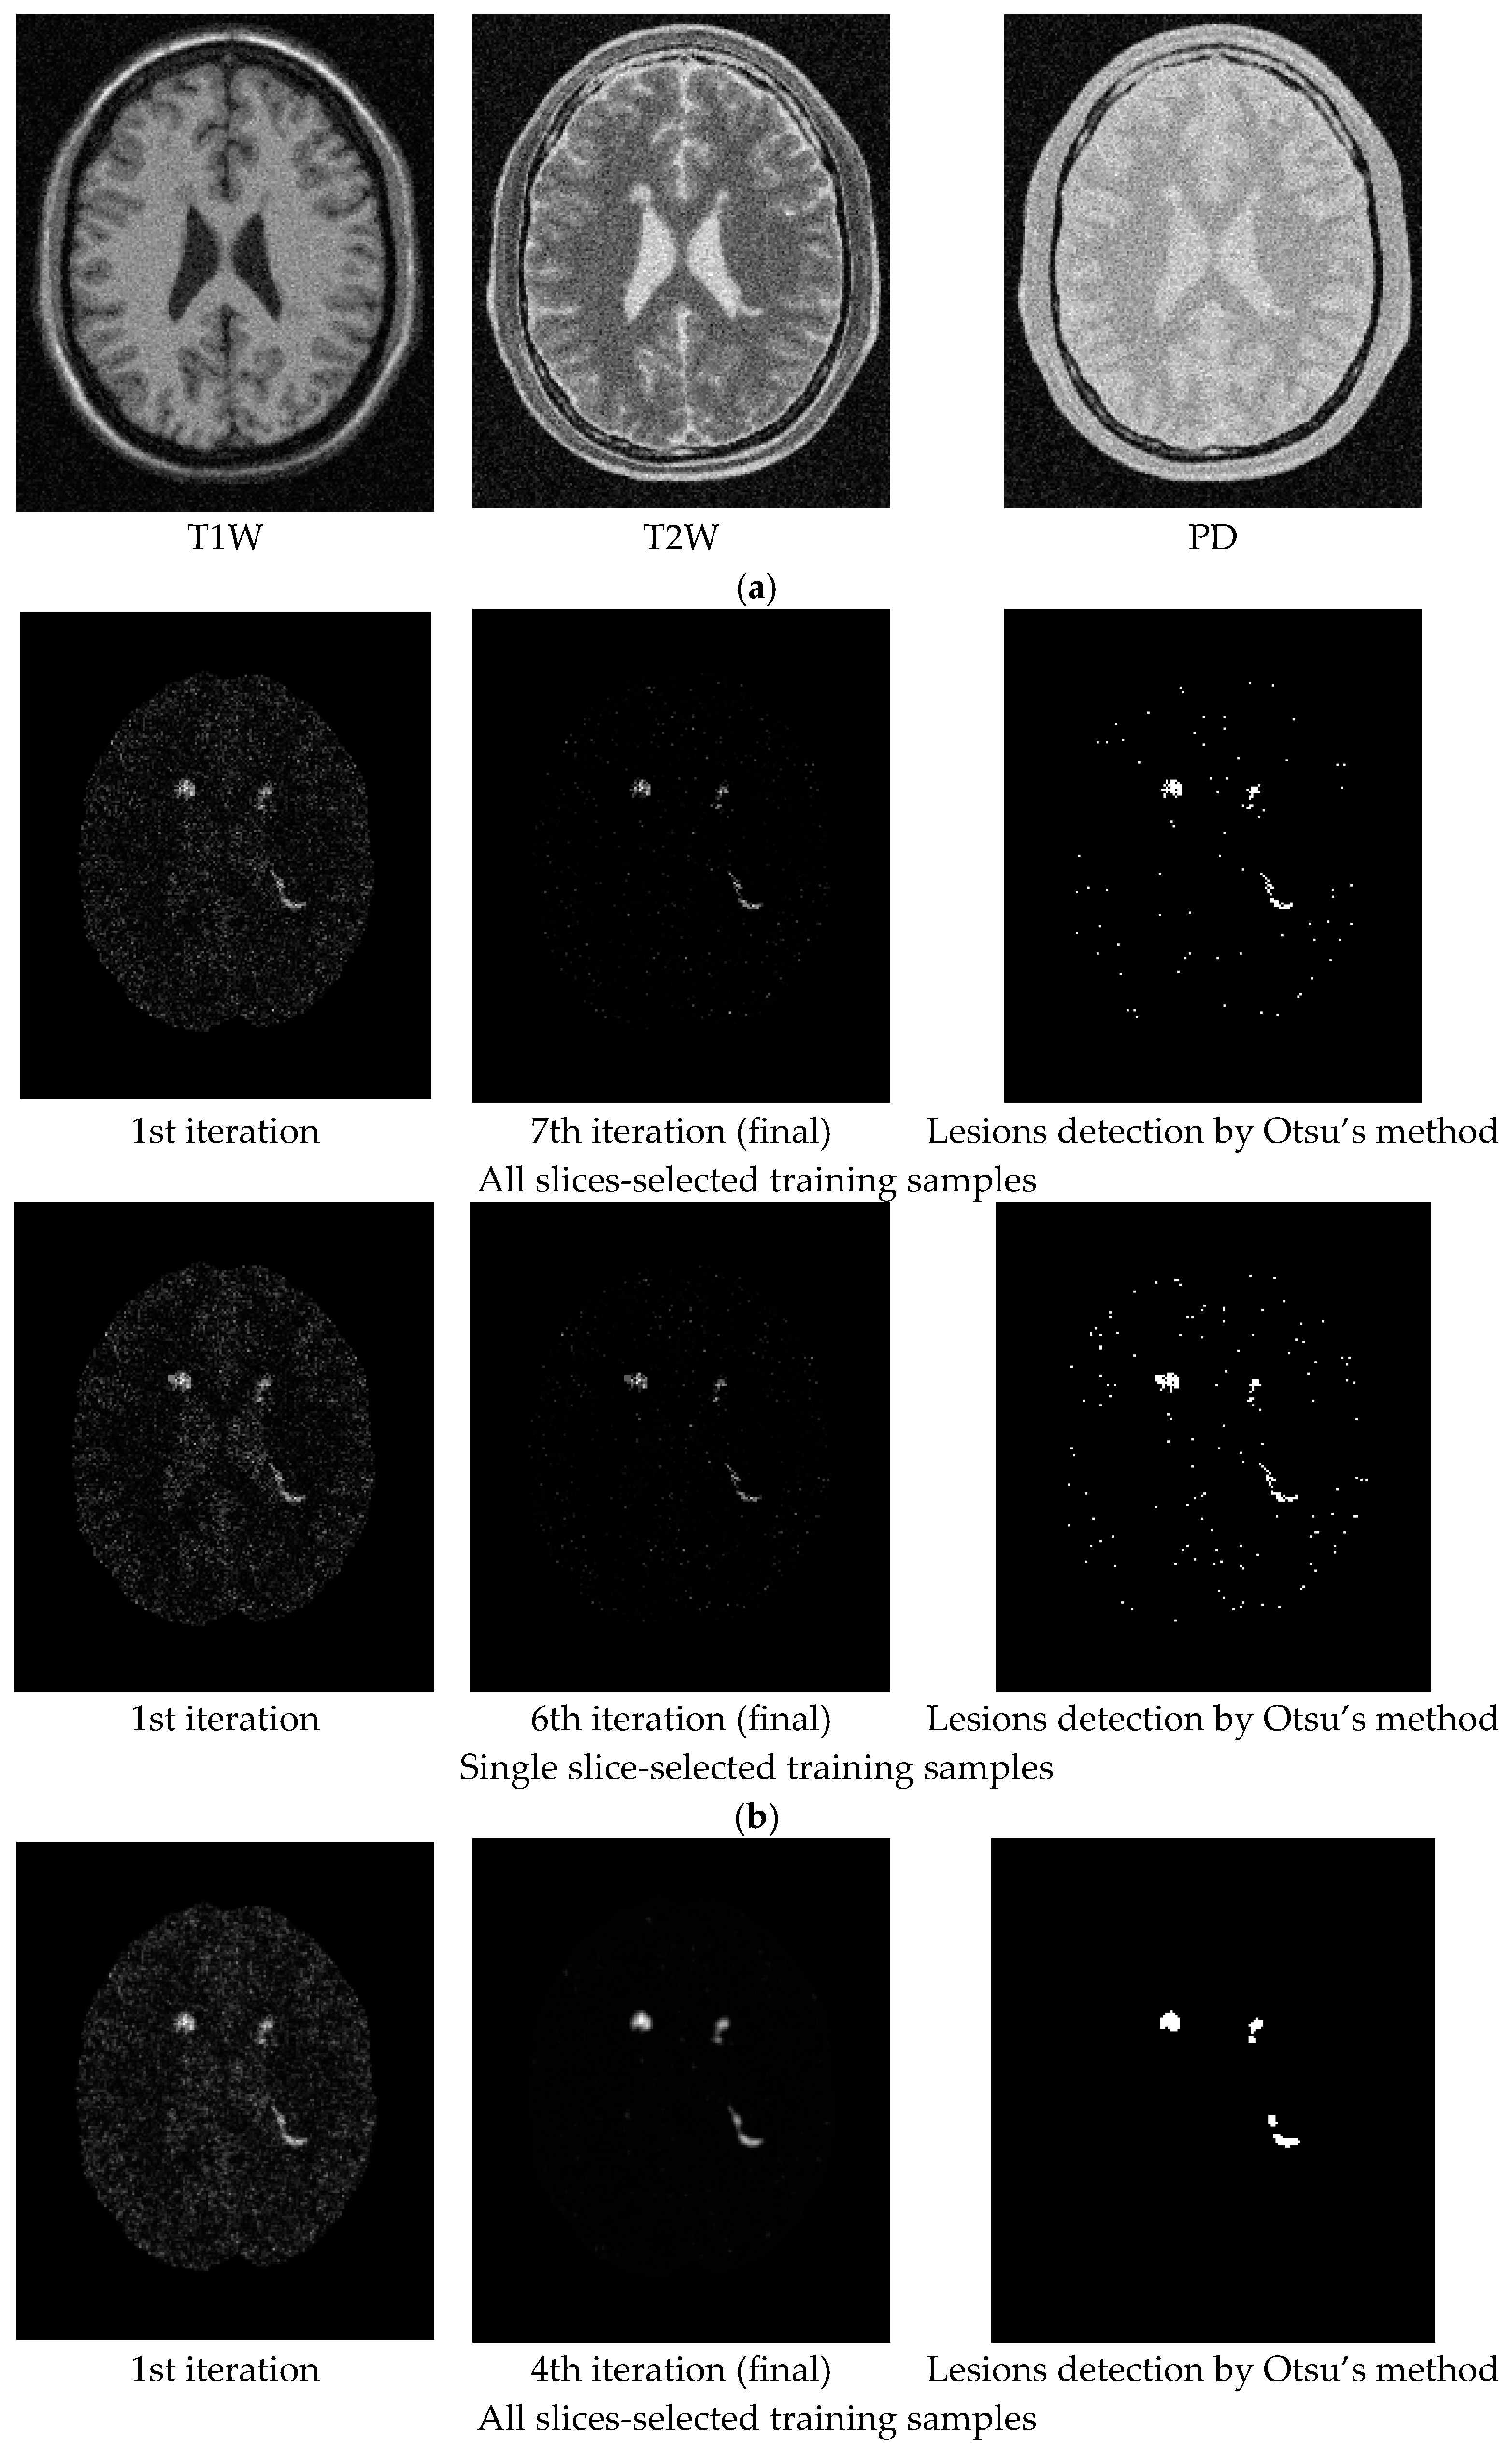

For an illustrative purpose, Figure 5, Figure 6, Figure 7, Figure 8, Figure 9 and Figure 10 only show detection results of WMH lesions of the 97th MR image slice with six levels of noise and 0% INU by two versions of CBEP-ICEM, using the Gaussian window size of specified by σ = 0.1 and the Gaussian window size of specified by σ = 0.5, referred to as CBEP-ICEM1 and CBEP-ICEM2, respectively, where two sets of training samples selected by all slices and the single 102nd slice were used to calculate the desired target signatures d to implement NBE-ICEM. As we can see by visual inspection against the ground truth in Figure 4d, CBEP-ICEM1 and CBEP-ICEM2 using two sets of training samples, i.e., all slices-selected and single slice-selected training samples, produced very close results and they both also performed better lesion detection than LST did.

Figure 12, Figure 13 and Figure 14 show the WMH lesion detection results produced by CBEP-ICEM2 and LST for three Fazekas grades, respectively, where Figure 12a, Figure 13a and Figure 14a are original T1W, T2W and FLAIR MR images; Figure 12b, Figure 13b and Figure 14b are iterative WMH lesion detection images by CBEP-ICEM2 along with final WMH lesion detection by Otsu’s method; and Figure 12c, Figure 13c and Figure 14c show comparisons between lesion detections by CBEP-ICEM2 and LST.

In comparison between CBEP-CEM1 and CBEP-CEM2, we found from Table 2 and Table 3 in the synthetic image experiments that, when the noise level is low (0%, 1%, 3%), CBEP-ICEM1 using a smaller Gaussian window performed better than CBEP-ICEM2 using a larger Gaussian window. However, when the noise level is high (5%, 7%, 9%), the conclusion is reversed, i.e., CBEP-ICEM2 performed better than CBEP-ICEM1. It is also interesting to note that CBEP-ICEM1 performed very poorly when noise level reached 7% and above and even worse than LST. Table 2 and Table 3 also shown that it was noise not INU that had an impact on lesion detection. On the other hand, CBEP-ICEM2 generally performed well regardless of noise level if DSI value was set to at least or above 0.8 compared to LST whose DSI values did not go beyond 0.8. The synthetic image experiments suggested that CBEP-ICEM2 was a better technique due to its robustness to noise level and ability in WMH detection.

In addition, based on the results of real image experiments from Figure 12, Figure 13 and Figure 14, there are three interesting findings. Firstly, the number of iterations carried out by CBEP-ICEM is always two for all three Fazekas grades. Secondly, in Figure 12c, CBEP-ICEM2 and LST performed similarly but quite different in Figure 13c and Figure 14c, where the areas of lesions detected by LST were much smaller than CBEP-ICEM2. Thirdly, the iterative images produced in Figure 12b, Figure 13b and Figure 14b by CBEP-ICEM2 showed that including spatial information captured by Gaussian-filtered CEM detection images did improve lesion detection, particularly edge and boundary pixels.